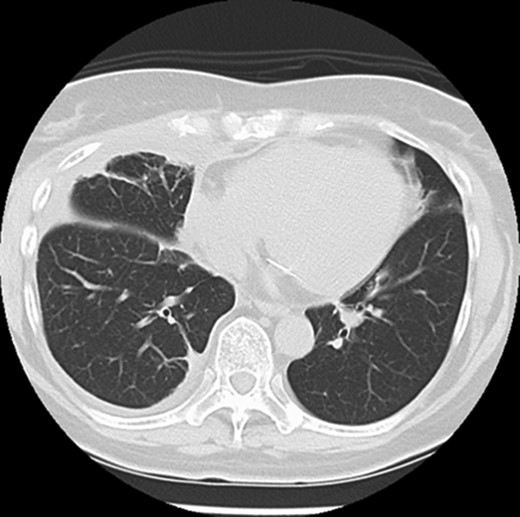

Five days after surgery, she complained of right chest wall pain and discomfort on inspiration. Computed tomography (CT) revealed that part of the right upper lobe of the lung had herniated through the right fourth intercostal space (Fig. 1). Lung hernia was diagnosed. The herniated lung was manually repositioned by compression bandages (Fig. 2). On postoperative Day 11, 6 days after recognition of the herniation, the lung hernia was not apparent on CT. The patient was discharged home without symptoms on postoperative Day 12.

Manual repositioning of the herniated lung by compression bandages.